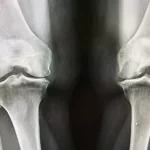

پیش از این که بخواهیم به بررسی راههای درمان دررفتگی کشکک زانو بپردازیم، بگذارید بررسی کنیم که چه زمانی میتوان گفت که کشکک زانو در رفته است؟ دررفتگی کشکک زانو یکی از آسیبهای شایع مفصل زانو است که زمانی رخ میدهد که استخوان کشکک از محل طبیعی خود در شیار استخوان ران خارج شود. این وضعیت با درد شدید، تورم، محدودیت حرکت و گاهی ایجاد صدای تق تق هنگام حرکت زانو همراه است و میتواند به دلیل ضربه مستقیم به زانو، پیچش ناگهانی پا، ضعف عضلات چهار سر ران یا ناهنجاریهای ساختاری مفصل رخ دهد. دررفتگی کشکک زانو اگر چه در ابتدا ممکن است خود به خود جای خود را پیدا کند، اما در صورت تکرار یا عدم درمان مناسب میتواند باعث آسیب به رباطها، غضروفها و ایجاد ناپایداری مزمن زانو شود.

در بسیاری از موارد دررفتگی کشکک، فرد ممکن است تغییر شکل قابل مشاهدهای در جلوی زانو احساس کند. کشکک ممکن است به یک طرف متمایل شود یا حتی به وضوح بیرون زده باشد. این جابجایی نشان دهنده خارج شدن استخوان از شیار طبیعی خود در استخوان ران است و با درد شدید همراه خواهد بود. تشخیص تغییر شکل زانو توسط پزشک، همراه با معاینه بالینی و در صورت نیاز تصویر برداری، برای تعیین شدت آسیب و انتخاب روش مناسب برای درمان دررفتگی کشکک زانو، ضروری میباشد.